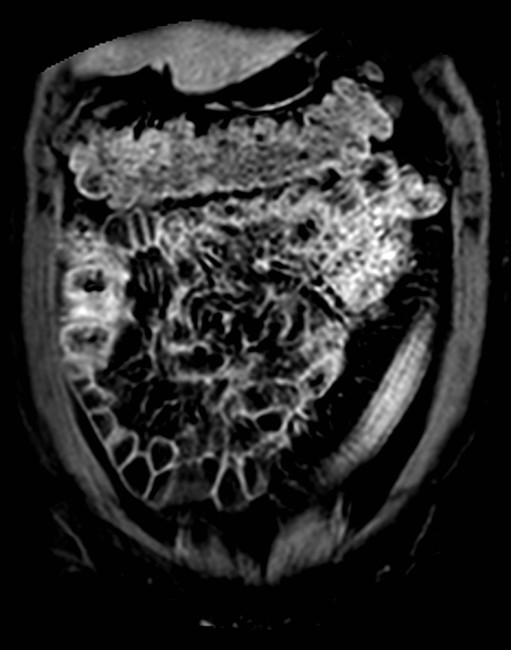

März 2017 von PD Dr. Peter Bannas aus Hamburg

Frage 1: Um welche Bildmodalität handelt es sich?

- a) MRT (native T2w-Sequenz sowie T1w-Sequenz mit Kontrastmittel)

- b) MRT (native T2w-Sequenz sowie native T1w-Sequenz)

- c) CT (portalvenöse und arterielle Phase)

- d) PET/CT (CT im Weichteilfenster und PET)

- e) CT (native und arterielle Phase)

Frage 2: Was führt in der benutzten Aufnahmetechnik am wenigsten wahrscheinlich zu Artefakten?

- a) Metallische Prothesen

- b) Luftansammlungen im Darm

- c) Bewegungen des Patienten während der Aufnahme

- d) Blutfluss

- e) Nierenzysten

Frage 3: Welche Struktur ist nicht erfasst?

- a) Colon descendens

- b) Colon ascendens

- c) Colon transversum

- d) Nieren

- e) Leber

Frage 4: Welcher Befund ist nicht vorhanden?

- a) Zielscheiben-Phänomen (Target-Sign)

- b) Ödem in der Submukosa

- c) Langstreckiger Verlust der Haustrierung

- d) Kontrastmittelanreicherung der Darmwand

- e) Pneumatosis intestinalis

Frage 5: Welche Diagnose stellen Sie?

- a) Colitis ulcerosa

- b) Colonkarzinom

- c) Lymphom

- d) Leiomyom

- e) Metastase

Preisfrage: Welche Erkrankung ist mit der Colitis Ulcerosa assoziiert?

- a) Primär biliäre Cholangitis

- b) Primär sklerosierende Cholangitis